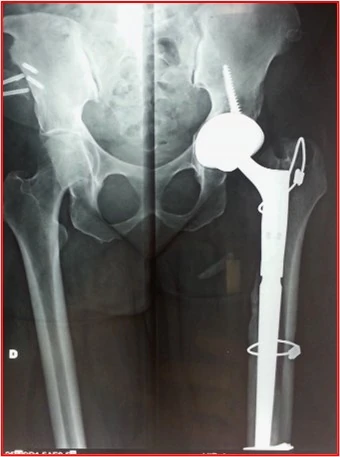

- Fratture periprotesiche: Rotture dell’osso vicino all’impianto, spesso conseguenti a traumi o cadute.

Tecniche di Ricostruzione Femorale

Per il femore, la stabilità si ottiene cercando l’ancoraggio distale dove l’osso è ancora solido:

- Steli da Revisione Modulari: Protesi composte da più componenti che il chirurgo assembla “su misura” durante l’intervento per adattarsi alla forma residua del femore.

- Ancoraggio Distale: Se la parte superiore del femore è riassorbita e troppo fragile, si utilizzano steli lunghi conici che si avvalgono e sfruttano la stabilità conico-diafisaria distale.